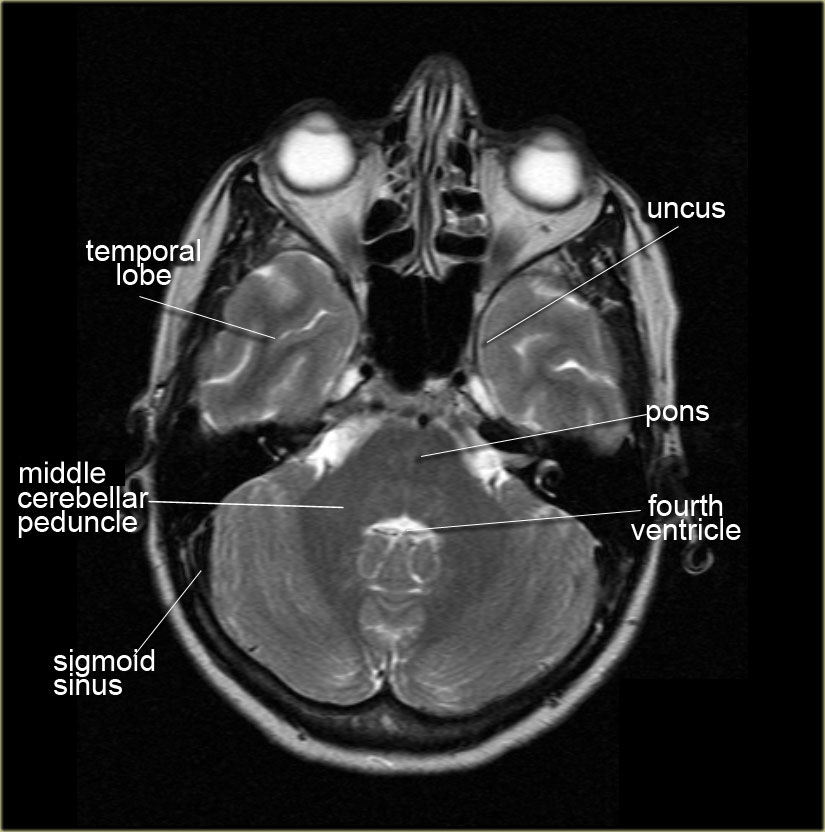

This video is from our cross sectional anatomy series. Cranial cross sectional anatomy is very important to know prior to analyzing a head ct.

Ct cross sectional anatomy. Only 9 left in stock order soon. Ct cross sectional anatomy of brain chest abdomen paranasal sinusus neck temporal bone heart slideshare uses cookies to improve functionality and performance and to provide you with relevant advertising. Symmetry is an important concept in anatomy and is almost always present in a normal head ct unless the patient is incorrectly positioned with the head cocked at an angle.

Once the normal structures are identified abnormalities can be detected and a diagnosis may be possible. Cross sectional anatomy timothy f. Cross sectional anatomy ct mri by govind b.

The Radiology Assistant Brain Anatomy

The Radiology Assistant Brain Anatomy